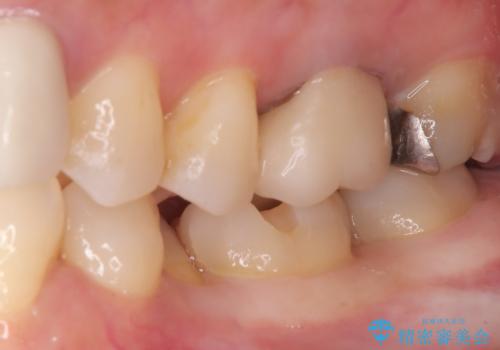

- 主訴:口を開けると所々入っている銀の詰め物が目立つので白い物にやり替えたい。

下顎大臼歯部に入っている保険適用のメタルインレーを、適合性と審美性の良いセラミックインレーでのやり替えとなりました。

メタルインレーを除去した際、古い裏層材やカリエスは除去し新たにCR裏層しています。

セラミックインレーセット時はラバーダム防湿を行っています。